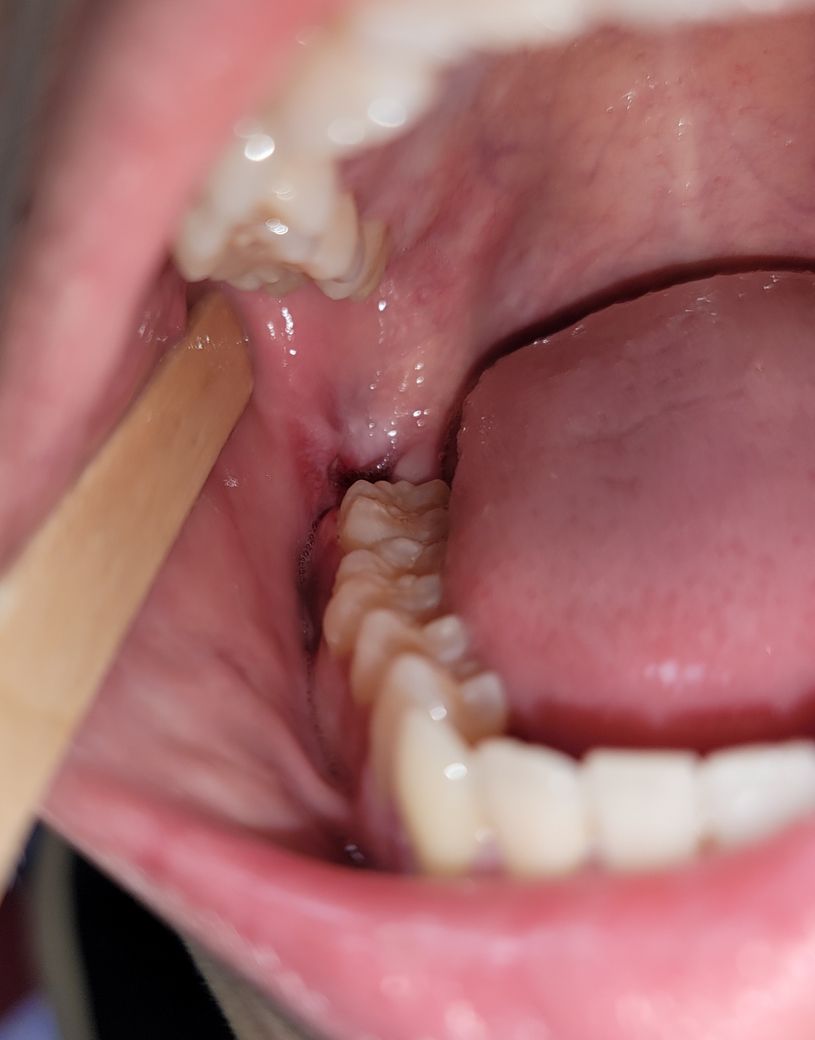

사랑니 발치 후 잇몸 실밥이 제대로 된건지 모르겠어요. 잘 아문거 맞나요? 반대쪽에 비해 너무 잘못된거 같아요

오른쪽 밑이 문제있고요 뽑은지 4~5일 됬습니다.

실밥을 한번만 묶었는데 좀 느슨한 느낌이 있고 묶은곳에서 조금 위쪽에는 안 묶인 느낌이라 양 옆으로 절개된 잇몸이 서로 맞닫지 않아 각자 상처가 치유되는 느낌입니다.

• 1번 째 사진